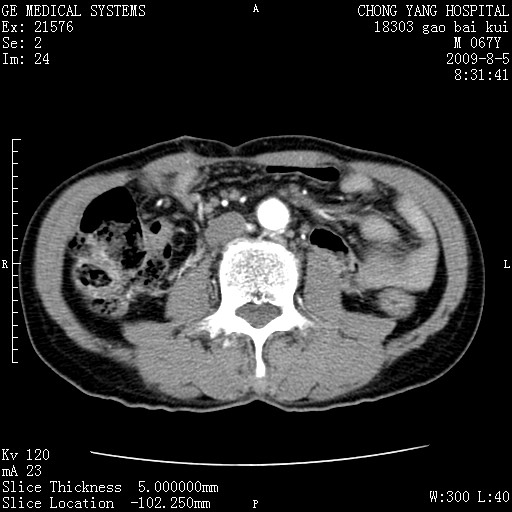

这个也过了,考虑胰腺钩突癌或壶腹癌,不除外胰管粘液乳头瘤伴胰管扩张,肝内胆管积气.

1)考虑胰头癌或壶腹癌并胰管扩张。2)肝外胆管扩张、积气,胆囊影未见;考虑术后改变。3)胃壁增厚?建议必要时行胃镜检查。

虑胰腺钩突癌或壶腹癌,不除外胰管粘液乳头瘤伴胰管扩张,肝内胆管积气.

考虑胰头癌并十二指肠受侵。